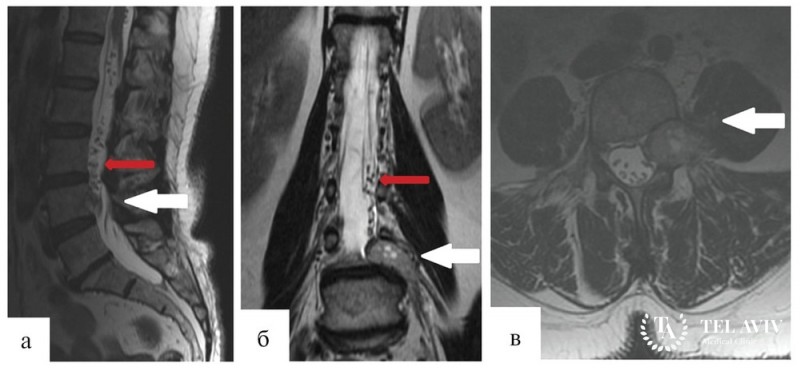

- МРТ или КТ;